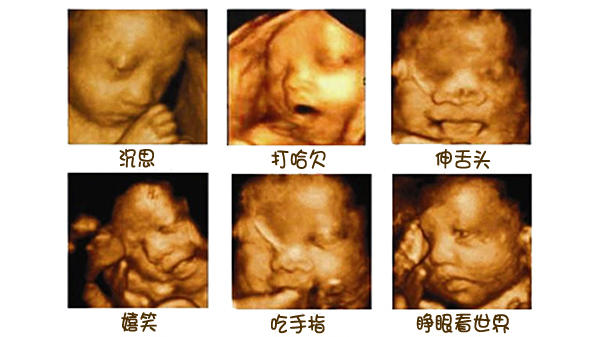

从第四个月开始,孕妈妈能感受到一定胎动,说明胎儿有生命体征了。等到28周,胎儿的四肢和面部已经逐渐趋于完善,能蹦能动了。若是个调皮外向的胎宝宝,甚至会在妈妈子宫内打拳呢。

所以,在探头勘测超声波影像时,胎儿在动。加上胎儿整个是泡在羊水里面,左动一下,右动一下,拍摄出来的成像难免会失真。